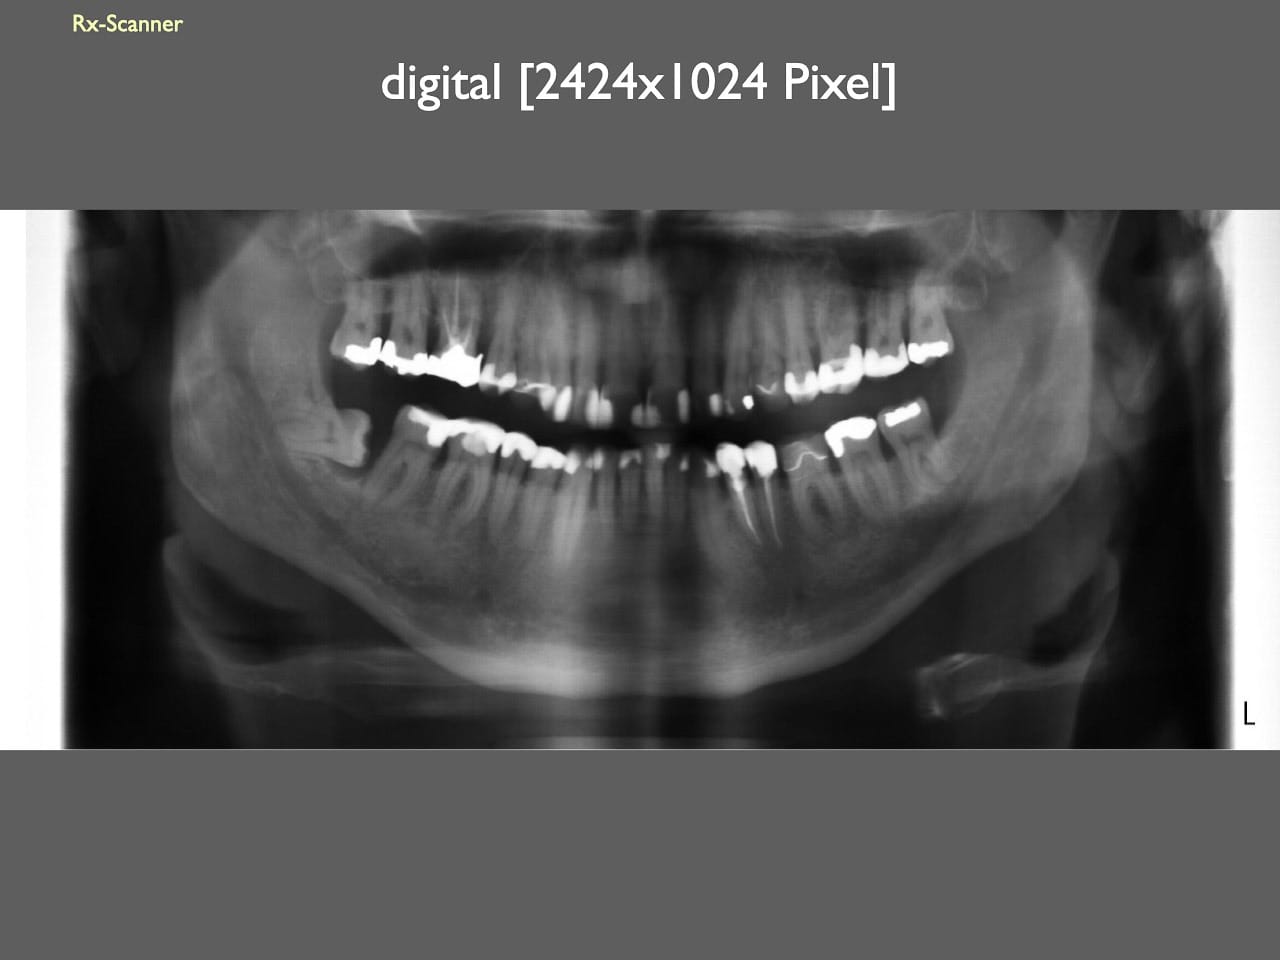

dental Scannen in der Zahnarztpraxis. Study Club vom 28.2.2010. Von peter portmann, Veröffentlicht am 28. Feb. 2010 — 3 min Lesezeit dokumentationfoto Auf dieser Seite Zahnarztpraxis-Trilogie zu Fotografie und Dokumentation Portrait Fotografie Scannen Scannen